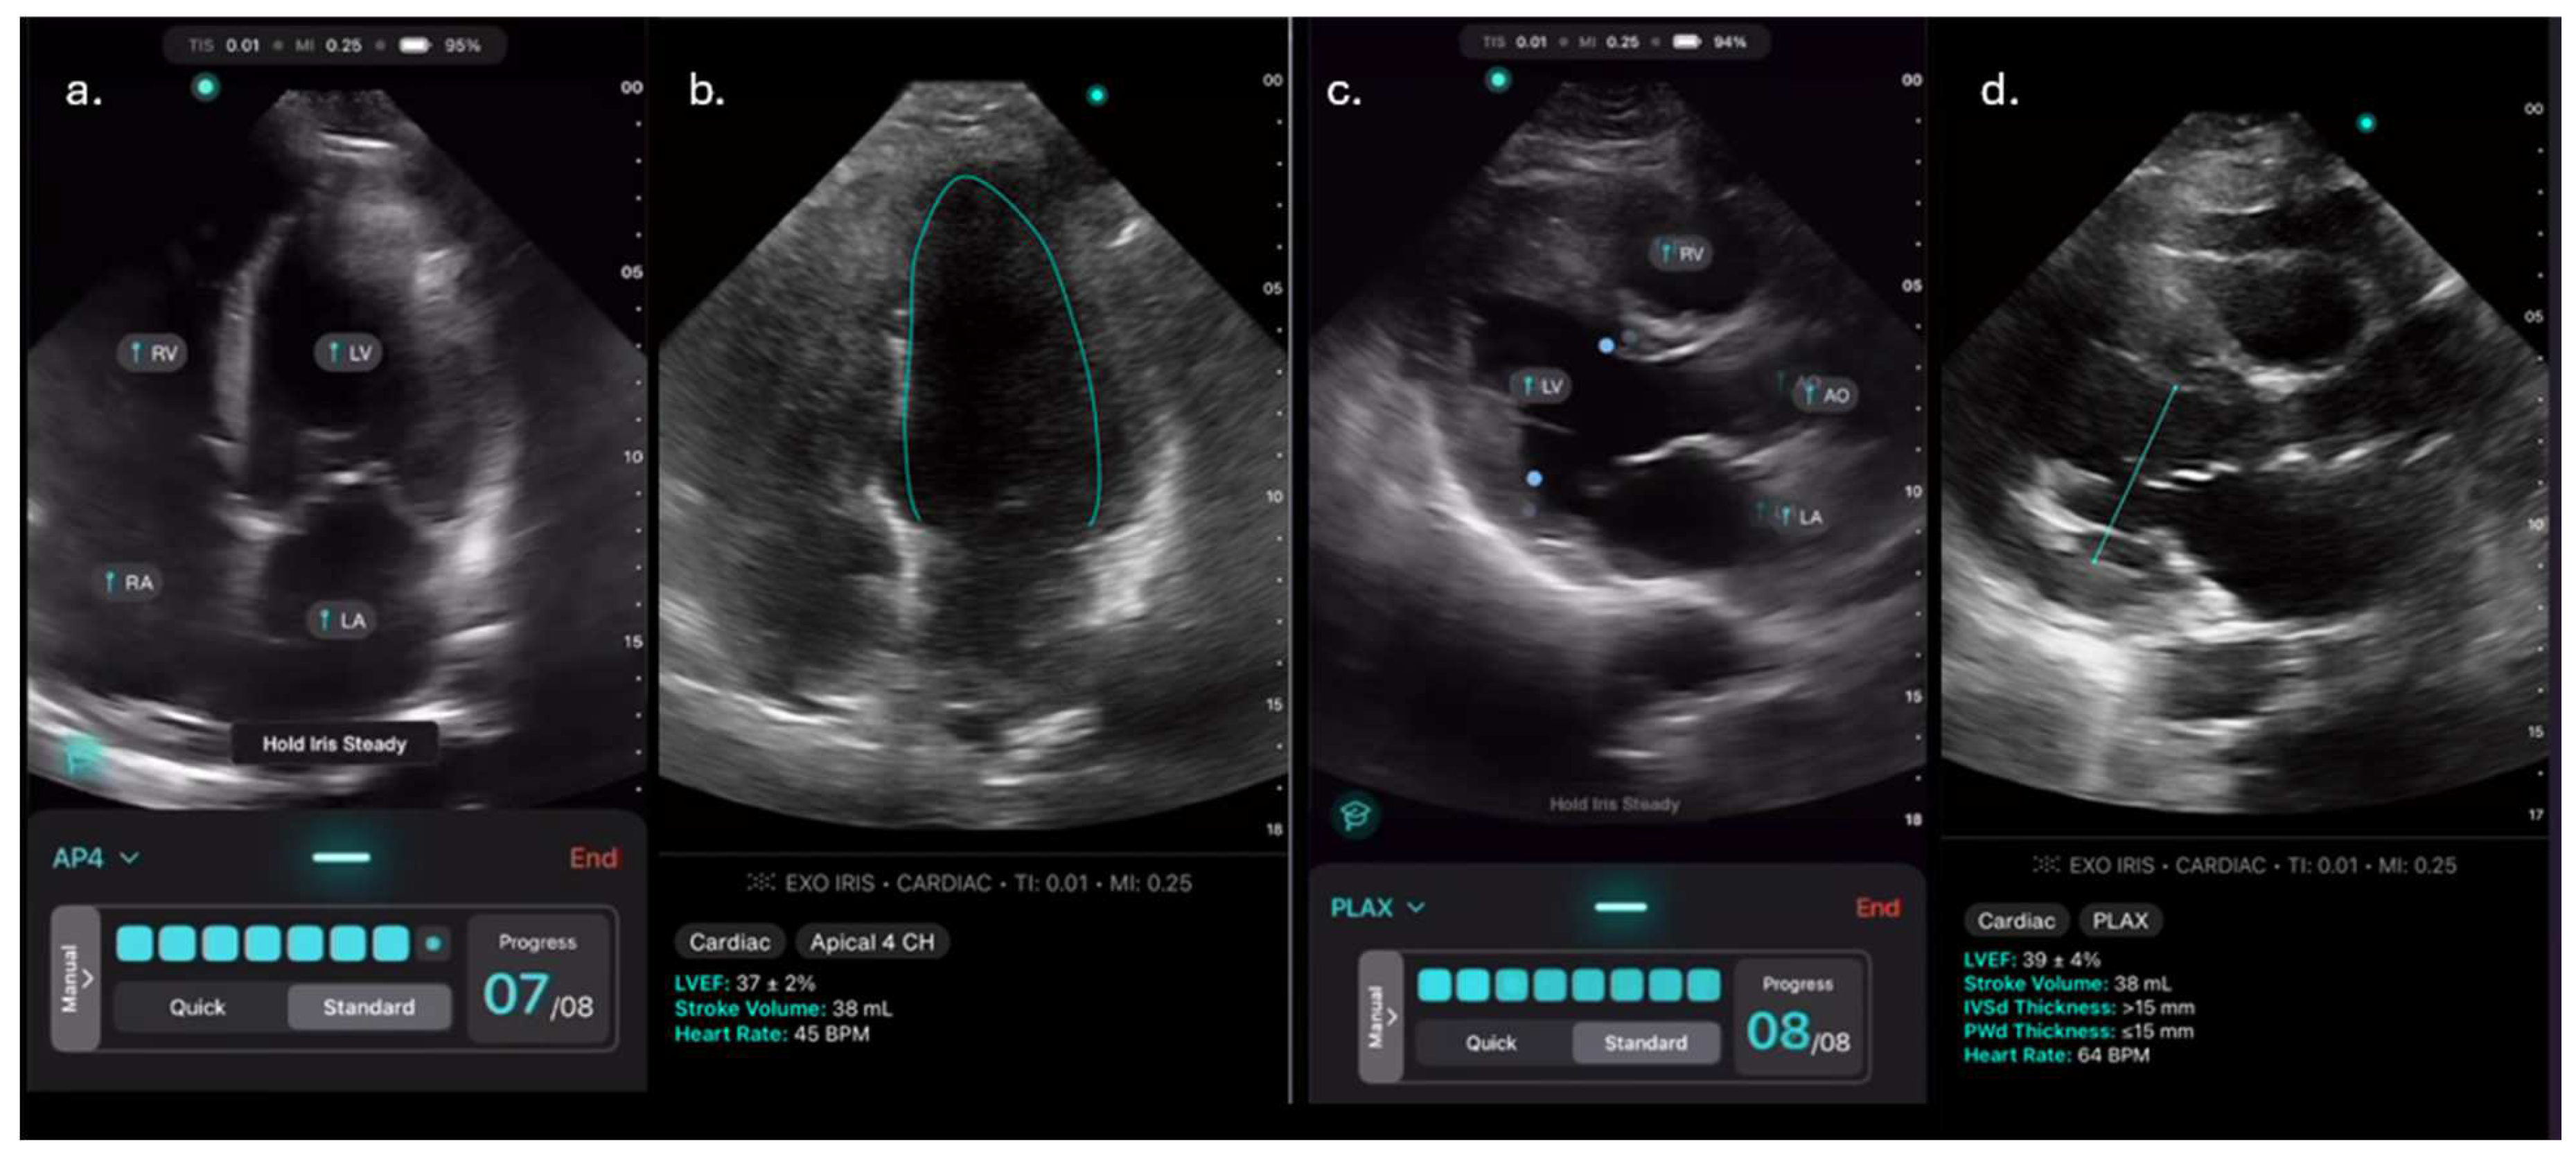

To assess feasibility and inter-user reliability of the AI-assisted echo, we scanned a small cohort of patients (Cohort 1) multiple times. In these patients, the expert and all available novices independently acquired their best attempts at PLAX and A4c views suitable for LVEF calculation using the AI-assisted tool on the Exo IRIS probe (Figure 1). Time to achieve diagnostic-quality images was recorded for the expert and novices. If any novice learner was unable to obtain views of sufficient quality to generate AI LVEF estimates within 5 minutes, the expert would step in to verbally assist until images were captured.

ExoAI provides an estimated LVEF and a confidence interval with an upper and lower bound (Figure 1b,d).

Figure 1. a-d. Images obtained using the AI-assisted tool on the Exo IRIS probe. a) Apical 4 chamber (A4C) view, b) AI-assisted LVEF of A4C, c) Parasternal long axis view (PLAX) d) AI-assisted LVEF of PLAX.